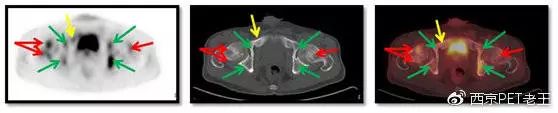

我们又把CT调整到骨窗,看骨骼病变的情况,可以看到全身绝大部分骨骼都有转移,但骨质结构破坏不明显(中列),说明这种是早期的骨转移,如下图:

红色箭头:胸椎及附件转移;黄色:肋骨转移;绿色:肩胛骨转移;蓝色:锁骨胸骨端转移

红色箭头:胸椎转移;黄色:肋骨转移;蓝色:胸骨转移

红色箭头:股骨头转移;绿色:髋臼转移;黄色:耻骨转移